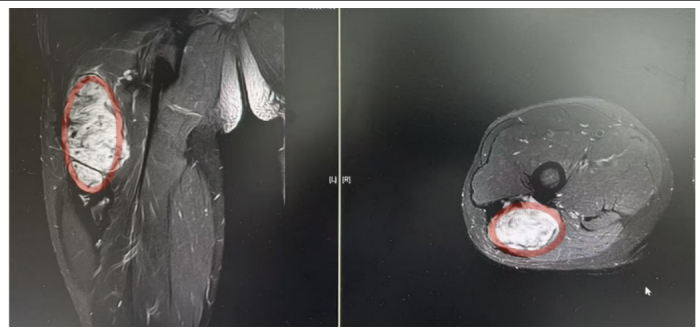

“患者入院后MR检查提示恶性肿瘤可能,肿块约10*2*2CM大小,经B超引导下行穿刺活检,病理提示:侵袭性纤维瘤病。”据手足显微外科副主任医师曾驰介绍,由于肿块较大,无法保守治疗,在完善术前准备后行瘤体切除术,手术顺利,术后患者恢复良好。

术前影像:红色标记部分为侵袭性纤维瘤